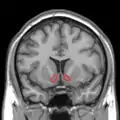

MRI coronal slice showing nucleus accumbens outlined in red